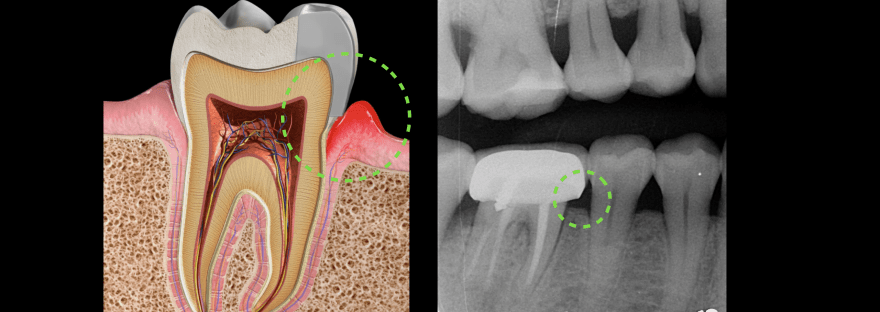

健康的牙齒跟牙齦幾乎是緊密貼合的。牙醫師會使用有刻度的牙周探針,針對每一顆牙齒進行探測檢查,沿著牙面弧度提放式行走,紀錄每一顆牙齒的牙周狀態。健康的牙周狀態,以探針探測,深度介於1-3mm之間,通常不會有滲血狀態出現,而是否有「探測時出血」,是牙齦健康的重要指標之一。當結石形成,發炎的現象越來越嚴重,患有牙周病的牙齒,探測深度會大於3mm,也就是進一步形成牙周囊袋,並且會逐漸加深。由於牙周病菌具有厭氧特性,氧氣較少的牙周囊袋正好成為孕育牙周病的溫床。牙周病菌不斷增生,散發出毒素,並且引發宿主免疫反應,造成齒槽骨吸收。當齒槽骨高度下降,便降低了對牙齒的支持力。如果置之不理、沒有妥善治療,經常導致牙齒喪失或需要拔除。